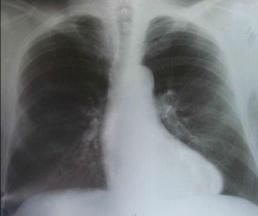

Рентгенологическое исследование.

Выявляет увеличение правого желудочка и левого предсердия, выраженность изменений сосудов малого круга, обусловленных развитием легочной гипертензии (рис. 8-2).

Рис. 8-2. Митральный стеноз При «пассивной» (венозной) гипертензии отмечается рас ширение

корней легких в виде гомогенной тени с нерезкими контурами.

При «активной» (артериальной) легочной гипертензии отмечается выбухание дуги легочной артерии в сочетании с расширением ее ветвей.